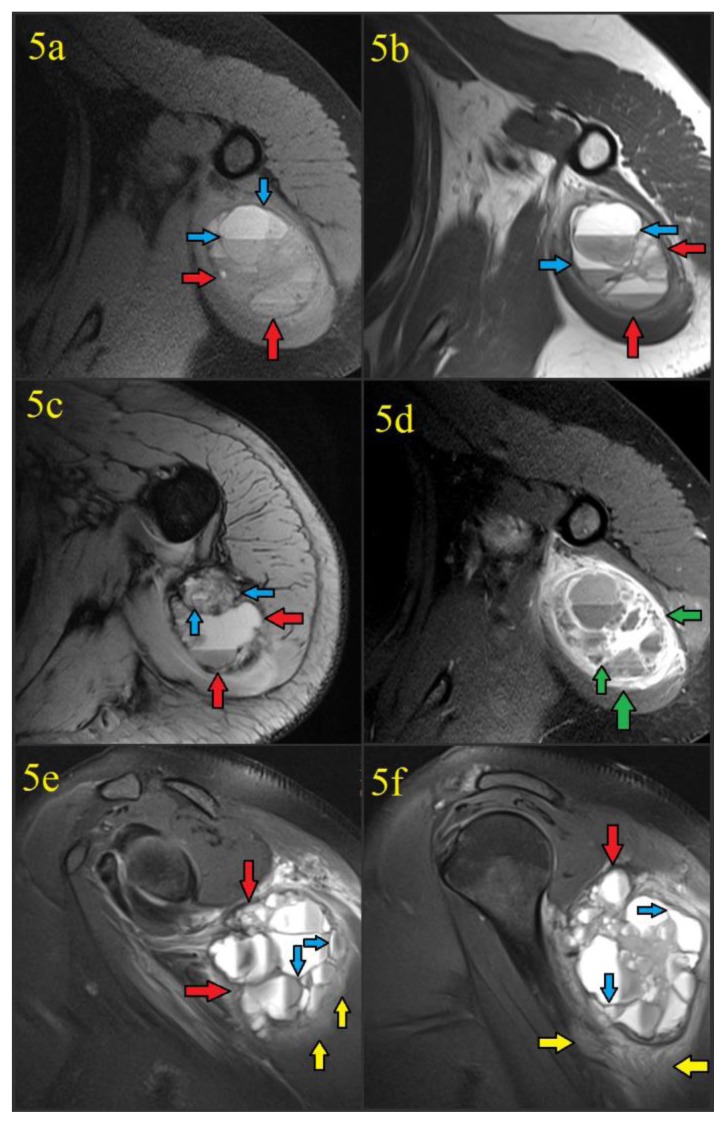

On CT, the mass again showed peripheral calcification. Central areas of hypodensity and a few calcified thin septations were also seen (figures 4a–4c). Magnetic resonance imaging (MRI) subsequently performed at an outside institution demonstrated a mass localized to the proximal triceps muscle and showed blood filled spaces of varying sizes with numerous fluid-fluid levels, T1/T2 hypointense septa, and a T1/T2 hypointense calcified rim with some septal enhancement (figures 5a–5f). There was no osseous involvement. A differential diagnosis of sarcoma and myositis ossificans was raised.

Figure 5.

41 year old female with a soft tissue aneurysmal bone cyst. The MR examination was performed 5 days after discovery of a calcified mass in the soft tissues of the left shoulder. Intravenous gadolinium contrast was administered prior to the acquisition of figure 5d.

Findings: Figure 5a: Noncontrast T1-weighted fat suppressed axial image acquired at the level of the upper triceps demonstrated a 6.8 (transverse) cm × 5.9 (anteroposterior) cm × 7.0 cm (craniocaudad) cm well-circumscribed mass (red arrows) with hypointense capsule/septations (blue arrows) and multiple fluid-fluid levels. No invasion of bone or muscular fat planes is seen.

Figure 5b: Proton density axial image acquired at the level of the upper triceps again showed the mass (red arrows) with hypointense capsule/septations (blue arrows) and multiple fluid-fluid levels, without bone invasion.

Figure 5c: T2-weighted axial image acquired at a slightly lower level of the triceps again showed the known mass (red arrows) with hypointense capsule/septations (blue arrows) and multiple fluid-fluid levels from hematocrit layering in the blood-filled cystic spaces.

Figure 5d: Post-contrast T1-weighted fat suppressed axial image acquired at the level of the upper triceps following the administration of intravenous gadolinium contrast showed avid enhancement of the soft tissue aneurysmal bone cyst fibrous capsule and septations (green arrows) in a “honeycomb” appearance. There was no enhancement of the blood filled cystic spaces themselves. Fluid-fluid levels were again seen.

Figures 5e and 5f: Proton density fat suppressed sagittal images provided craniocaudad demonstration of the 6.8 (transverse) cm × 5.9 (anteroposterior) cm × 7.0 cm (craniocaudad) cm well-circumscribed soft tissue ABC (red arrows) with hypointense capsule/septations (blue arrows) and multiple fluid-fluid levels. Edema was seen in the adjacent triceps and deltoid musculature (yellow arrows).

Technique: MR scanner and contrast details are unknown since the examination was performed at an outside institution. Parameters were as follows: figure 5a: TR=720.0, TE=9.1, FA=170.0, figure 5b TR=3500.0, TE=33.0, FA=160.0, figure 5c: TR=577.0, TE=15.0, FA=30.0, figure 5d: TR=720.0, TE=9.1, FA=170.0, figures 5e and 5f: TR=3100.0, TE=42.0, FA=150.0.